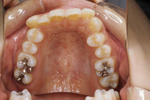

矯正の症例

1) 矯正前の状態

叢生(そうせい…歯がデコボコしたり、重なりあって生えていたりする状態)

開咬(かいこう…奥歯はしっかり噛んでいるが、上下の前歯が噛まずに隙間がある状態)